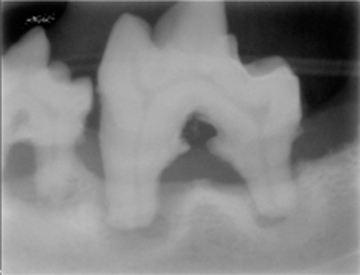

La periodontitis se clasifica como “Periodontitis leve” cuando el tejido óseo se ha destruido máximo en el tercio cervical; “Periodontitis moderada” cuando la destrucción ósea ha llegado al tercio medio de la raíz y “Periodontitis severa” cuando la destrucción ósea ha llegado al tercio apical de la raíz. La movilidad dental ligera aparece en la periodontitis moderada y la movilidad dental excesiva aparece en la periodontitis severa.

Haz CLICK sobre la imagen para ver descripción.